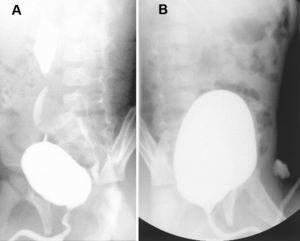

En los 4 niños con duplicación renoureteral, 10 uréteres presentaban RVU. El tratamiento con una inyección endoscópica de polidimetilxilosano corrigió el reflujo en siete unidades ureterales (2 pacientes) (fig. 2).

Figura 2. A) Cistouretrografía en paciente portador de duplicidad renoureteral bilateral con reflujo vesicoureteral bilateral (RVU). B) Cistouretrografía del mismo paciente tras la inyección endoscópica subureteral de polidimetilxilosano, sin evidencia de RVU.